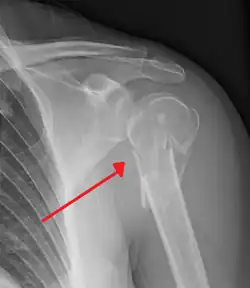

A fracture of the greater tuberosity as seen on AP X ray -

A fracture of the greater tuberosity of the humerus -

Fracture of the greater tuberosity of the humerus -